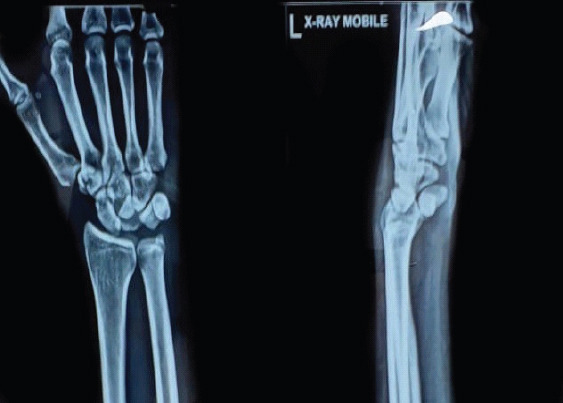

Case report: We present a case of a 40-year-old polytrauma patient who sustained multiple injuries following a road traffic accident. His acute injuries were predominantly treated, while a neglected isolated lunate dislocation remained undiagnosed. Three weeks later, the patient presented with acute carpal tunnel symptoms - severe wrist pain, numbness, and weakness in the distribution of the median nerve.Physical examination demonstrated tenderness over the volar wrist, reduced range of motion, and a positively elicited Phalen's and Tinel's sign. Radiographs and nerve conduction studies confirmed a neglected volar lunate dislocation causing compression of the carpal tunnel. Surgical intervention was performed through a combined dorsal and volar approach. Open reduction and internal fixation were followed by decompressive carpal tunnel release.Postoperatively, the patient recovered well, with resolution of symptoms and return of nearly normal wrist motion and grip strength at 1-year follow-up.